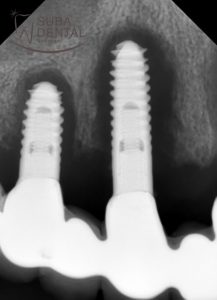

The dark shadow around the implants (peri-implantitis) in the intraoral X-ray scans.